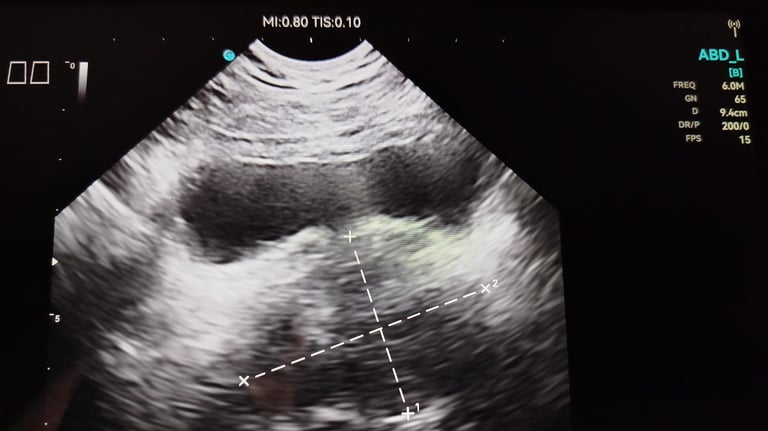

Ecografía

Diagnóstico por imagen avanzado en la comodidad de tu salón